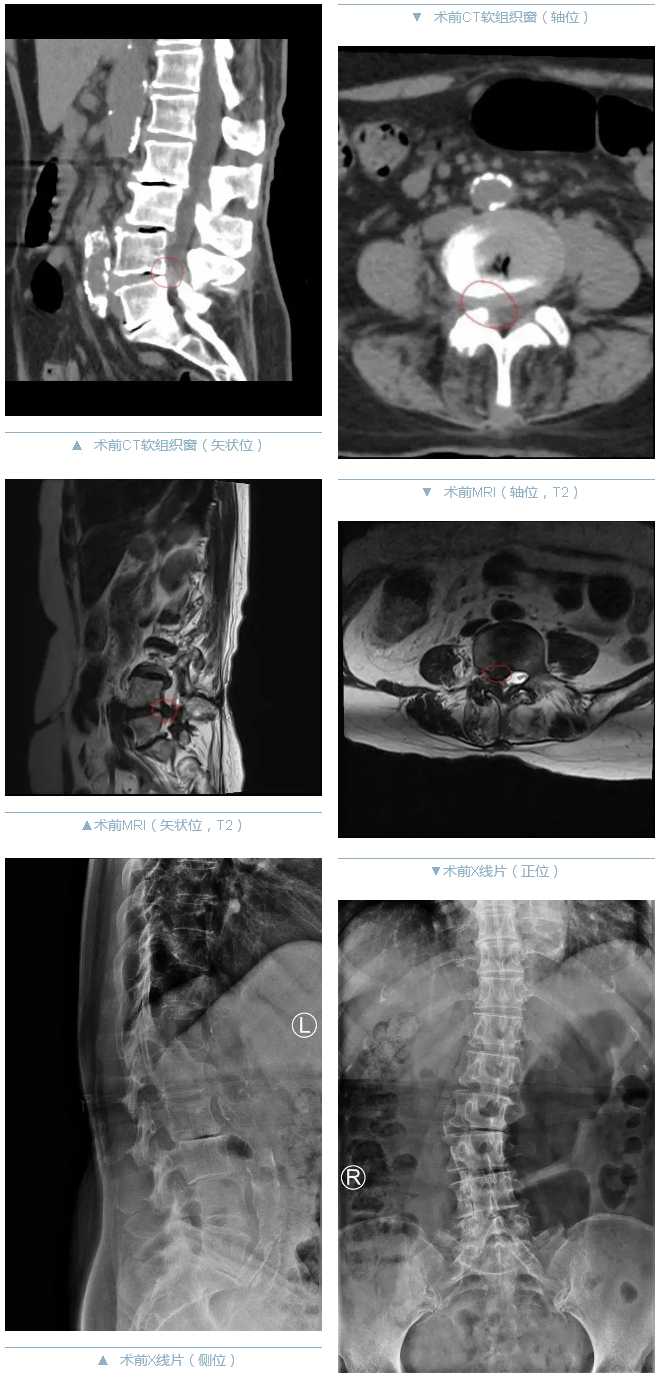

77岁的王奶奶,间断腰背部疼痛伴右下肢放射痛30余年,两个月前劳累后症状加重,导致右下肢严重的疼痛及麻木、肌力下降,严重影响了日常生活。在当地医院确诊为腰椎间盘突出症(L4/5)合并腰椎管狭窄、脊柱侧凸畸形及椎后小关节重度骨性关节炎,应用活血化瘀、营养神经等药物治疗辅助理疗后,症状并未得到缓解。王奶奶先后就诊于市里多家三甲医院,均告知需要行开放手术治疗,但因为王奶奶年龄偏大,又同时合并高血压、冠心病、心律失常等慢性疾病,最终都未能得到满意的治疗。最后,王奶奶在家人的陪伴下来到了我院骨中心脊柱外科,脊柱微创中心副主任医师许崧杰对老人进行了细致的查体,并仔细阅读了患者的影像学资料,经过缜密的思考评估,最终决定采用椎间孔镜技术为老人进行微创手术治疗。

王奶奶住院后,脊柱外科微创团队完善了老人相关的影像学检查,明确了患者的症状节段,精确缜密地测量了患者的影像学相关数据。最终,选定了对患者腰4/5节段右侧行微创椎间孔镜下关节突成型+髓核摘除+神经根减压+纤维环成型术,并针对手术确定了减压节段、减压范围、通道置入方式等,精确到每一个“点”。这个手术对于操作者有着极高的技术要求,一丝一毫的偏移都有可能导致穿刺失败、通道无法建立、显露髓核失败、神经根损伤、脑脊液漏等严重的并发症,直接导致患者神经损伤、瘫痪的风险。